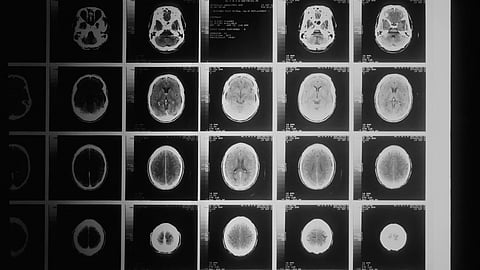

To fill that gap, Bejarano, Joyce and colleagues conducted a deep analysis of the molecular features and gene expression patterns of cells that form the blood-brain barrier in noncancerous brain tissue and metastatic brain tumor samples freshly isolated from patients with the three major cancers. They then focused on endothelial cells (ECs), which line the inner vascular surface, and mural cells—pericytes and smooth muscle cells—that swaddle and stabilize blood vessels.

Their analysis revealed significant differences between gene expression patterns in these cells and those of the same cells obtained from noncancerous brain tissue. The patterns suggested multiple aberrations in tumor vessels, including problems in the intercellular junctions and adhesiveness of ECs and mural cells—reflecting the well-known “leakiness” of tumor blood vessels—and their elevated interactions with certain subsets of immune cells. These findings, and others obtained using advanced imaging methods, were recapitulated in studies conducted in mouse models of brain metastasis.